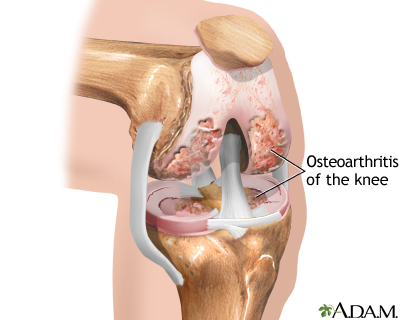

The most common cause of knee damage that leads to knee replacement is osteoarthritis. Osteoarthritis is a degenerative disease of the bones of the knee. It causes the surfaces of the knee joint to become irregular and rough, preventing smooth painless motion of the knee joint.